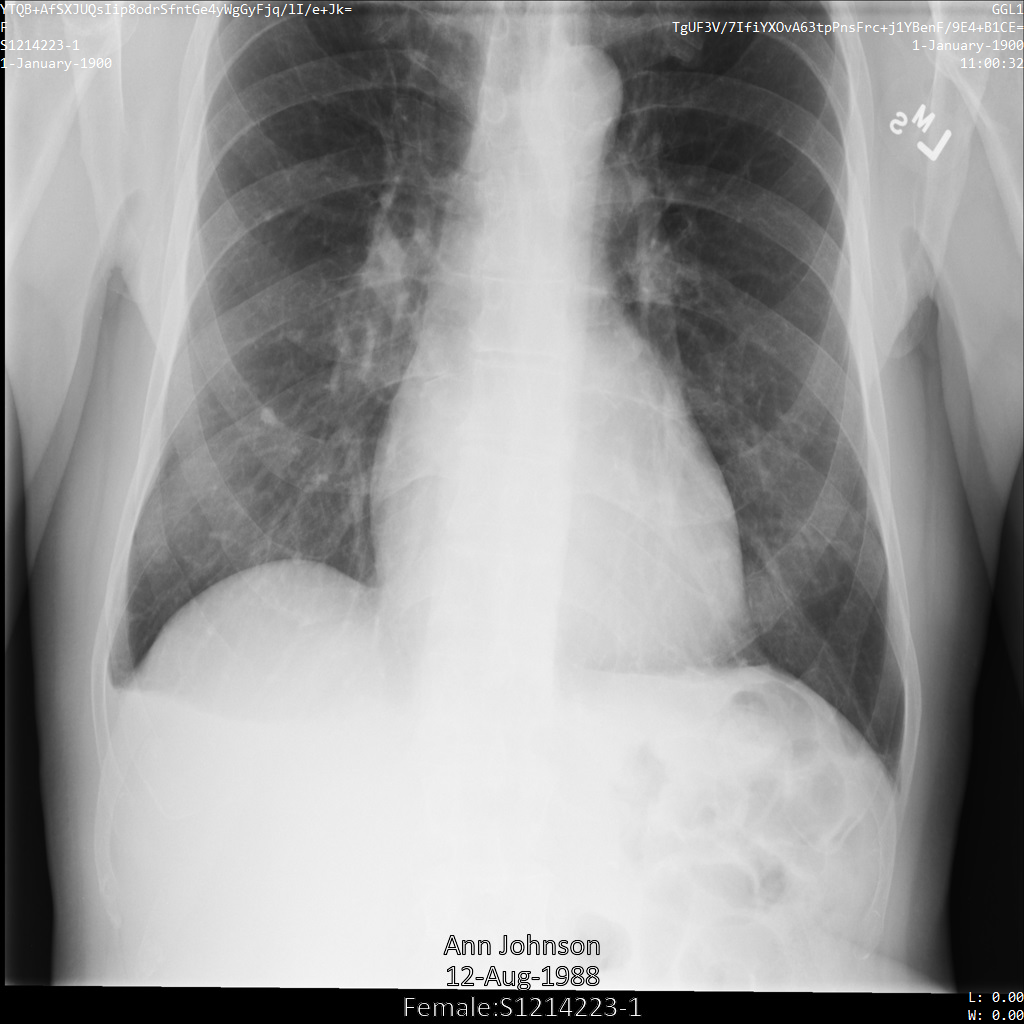

Después de enviar la imagen a la API de Cloud Healthcare mediante el perfil de filtro de etiqueta ATTRIBUTE_CONFIDENTIALITY_BASIC_PROFILE, la imagen aparece de la siguiente manera. Mientras se ocultan los metadatos que se muestran en las esquinas superiores de la imagen, permanece la PHI quemada que se encuentra en la parte inferior de la imagen.

Para quitar también el texto grabado, consulta Cómo ocultar el texto grabado de las imágenes.